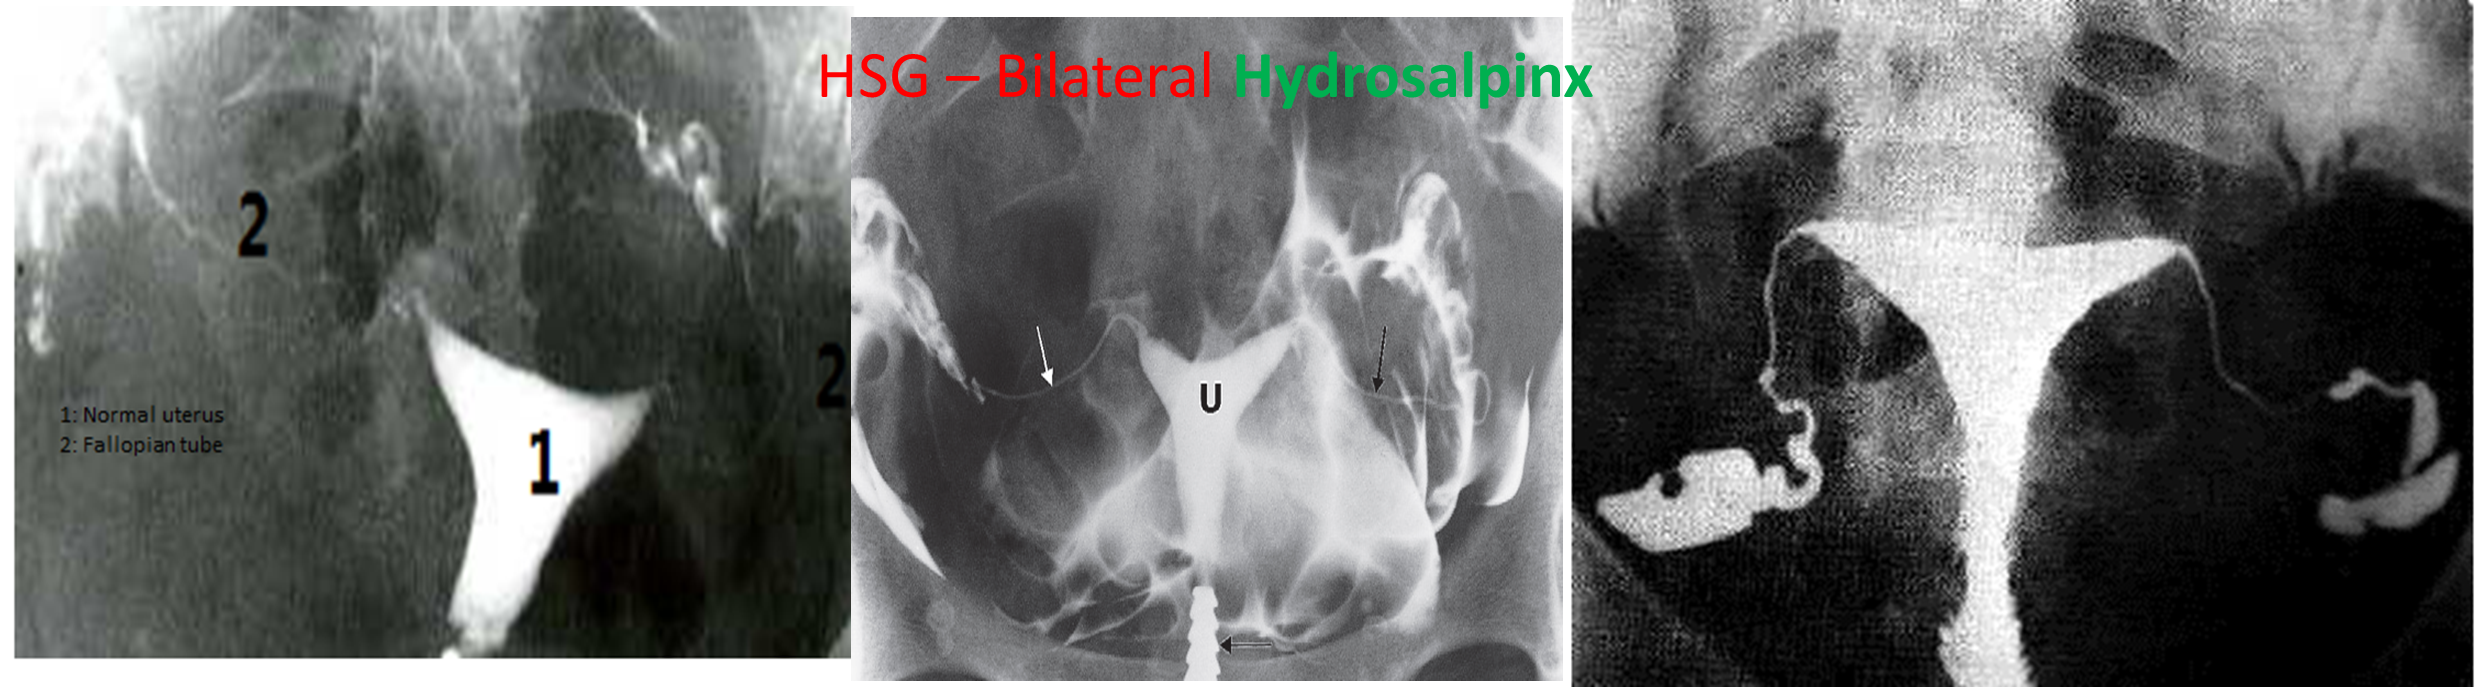

An imaging technique involving the injection of contrast dye into the cervical canal and serial radiographs to evaluate the uterine cavity and morphology/patency of the fallopian tubes

HSG Reference radiologic method for assessing tubal patency